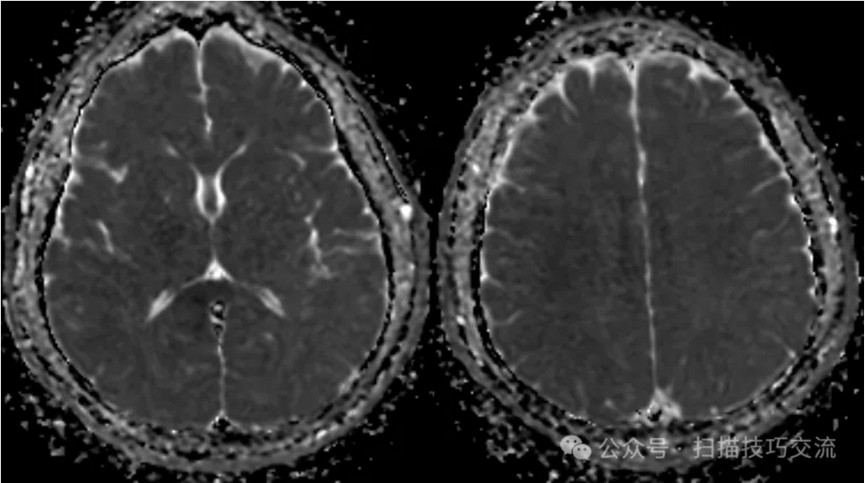

临床申请:颅脑平扫,静脉成像,磁敏感成像,颅内静脉血管黑血成像。

SWAN未见异常。